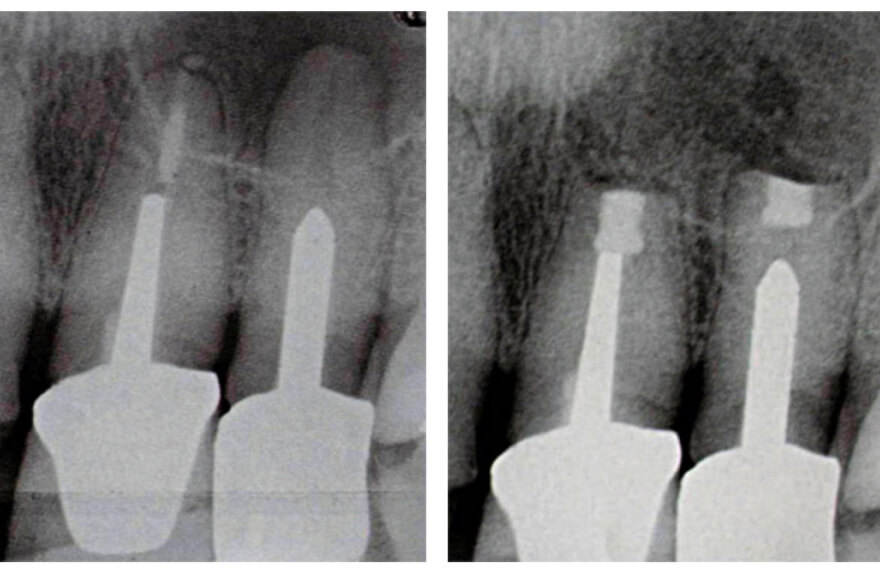

Мікрохірургічна операція, що спрямована на збереження зуба шляхом видалення вогнища інфекції навколо кореня зуба з частинкою кореня і пломбування каналу зі сторони кістки.

Показання: зуби з якісно пролікованими каналами, але запалення навколо кореня не зникає; коронки або мостовині протези на зубах з запаленням навколо кореня; масивний штифт в зубі, вилучення якого може значно пошкодити зуб.

Операція проводиться з мікроскопом та по протоколу, що технічно більш складний для лікаря, але дозволяє збільшити успіх лікування до 90% і зберегти зуб від видалення. Адже свій зуб завжди кращий за штучний замінник. Особливо, якщо це естетична ділянка.

Перевага апікальної хірургії перед імплантацією – це терміни виконання – один візит з тривалістю 1-2 години.

З яких етапів складається ця операція:

1 - діагностика: комп’ютерна томографія;

2 - знеболення – місцева анестезія; за бажанням пацієнта: наркоз;

3 - роблять невеличкий розріз ясен та віконце в кістковій тканині діаметром 5 мм;

4 - відсікають 3 мм кінчика кореня;

5 - промивають антисептиками та пломбують кореневий канал зі зворотнього боку інертними матеріалами;

6 - накладання швів.